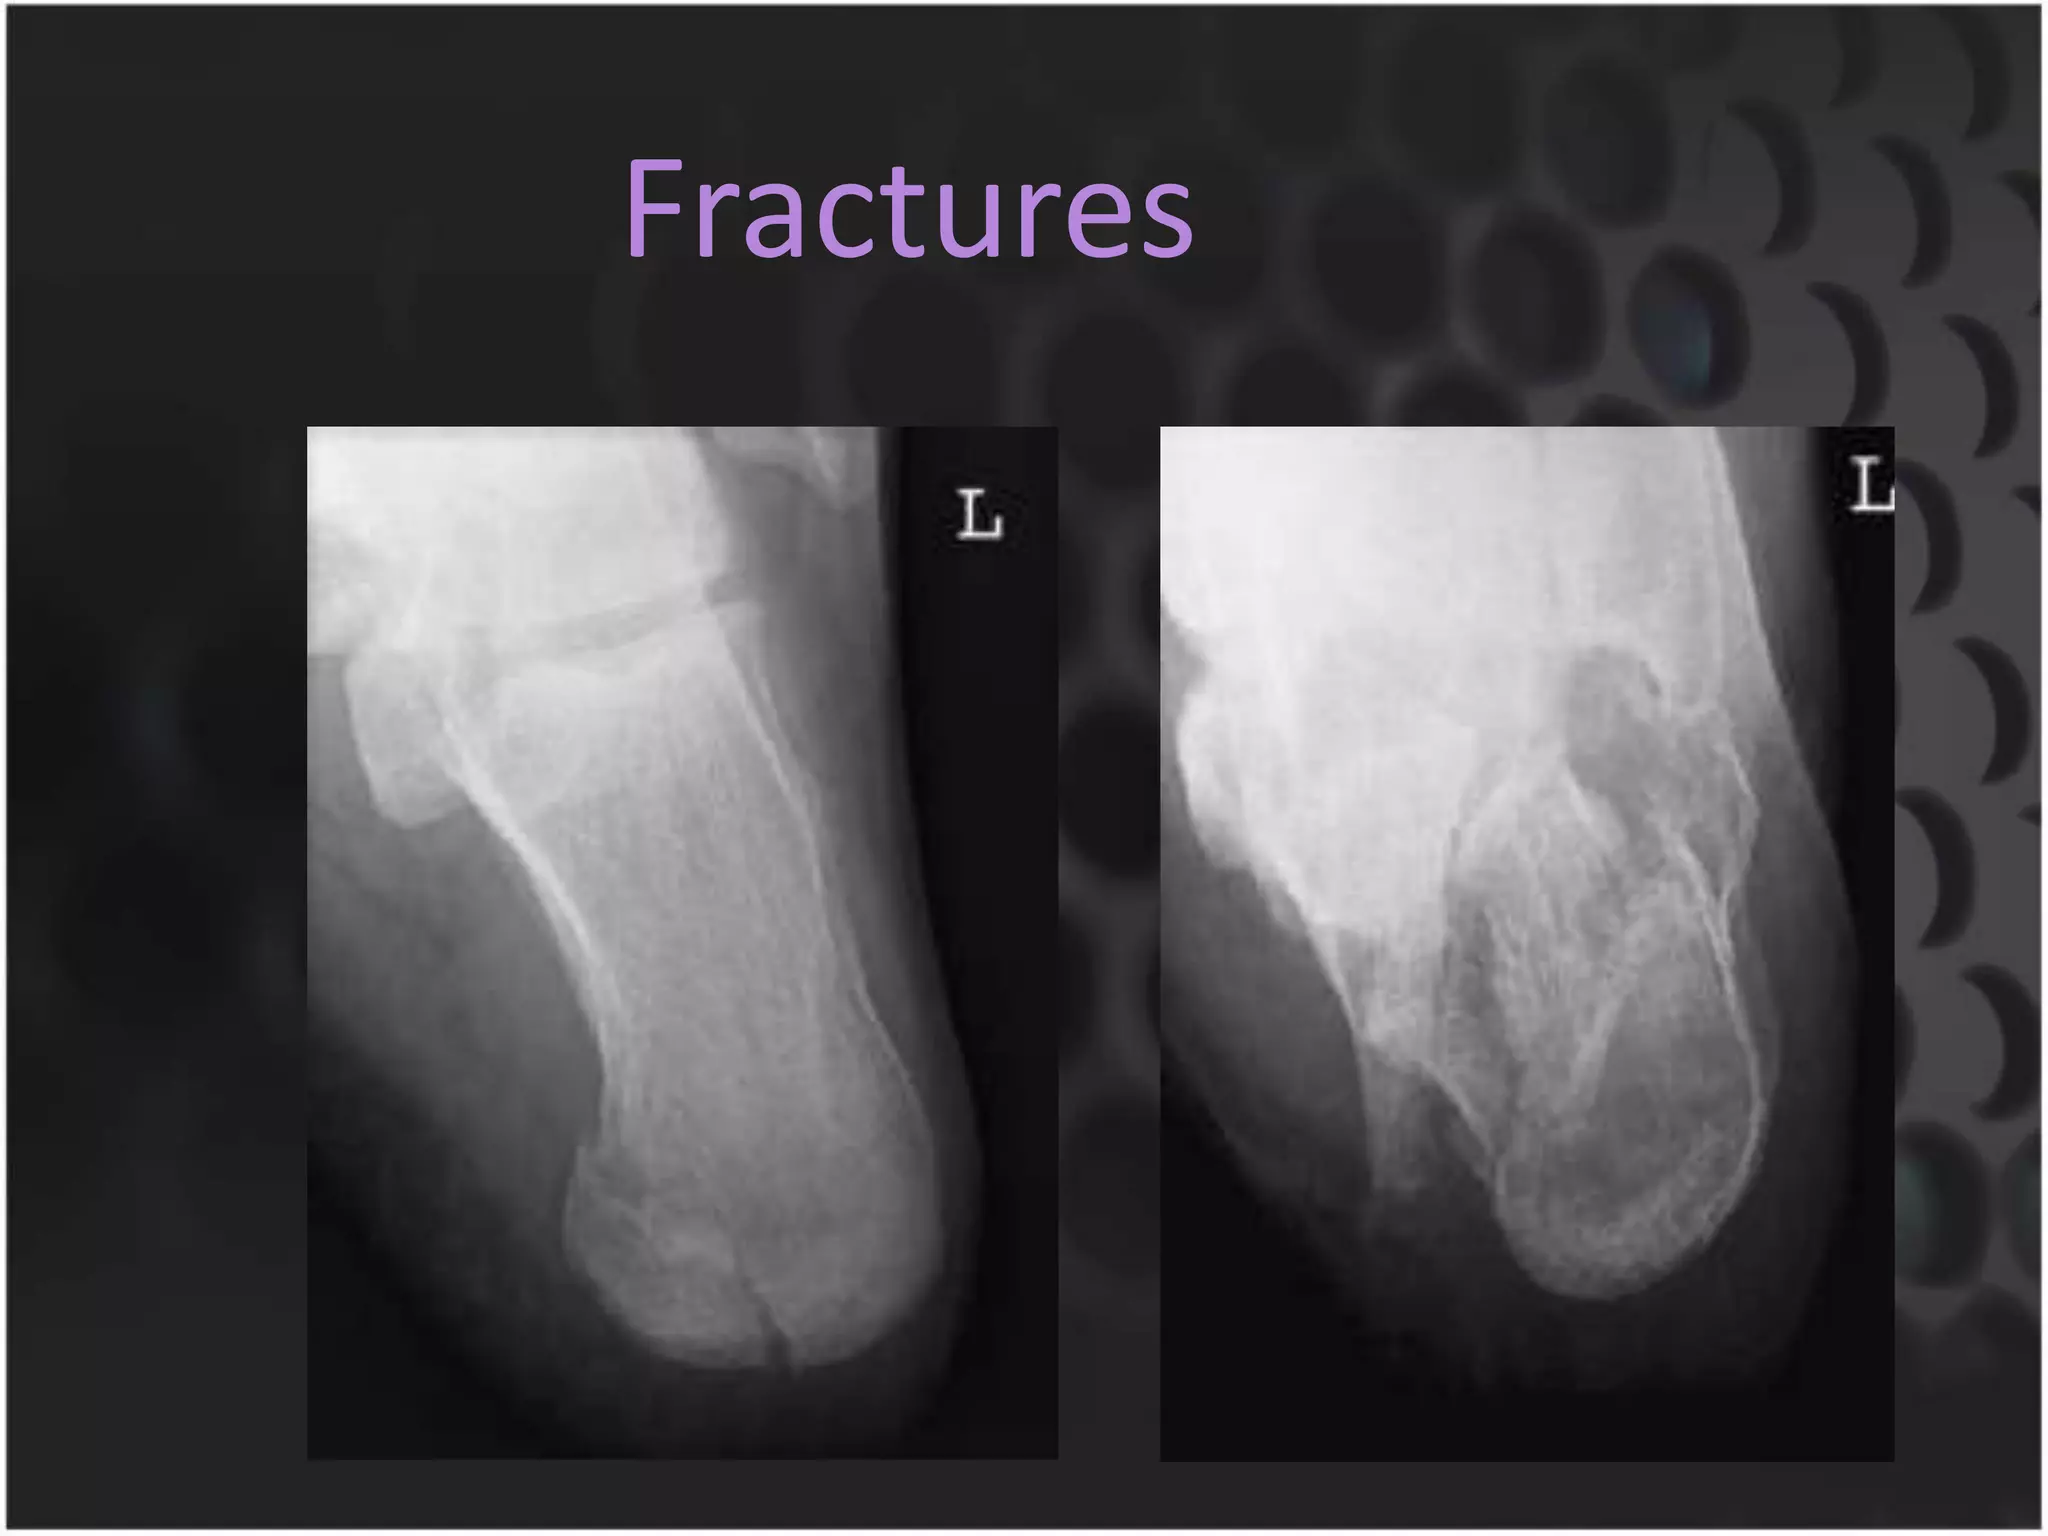

This document discusses trauma to the pelvis, hips, knees, ankles, and feet. It covers anatomy, imaging techniques, and types of fractures and dislocations that can occur in these areas. The types of fractures discussed include pelvic ring fractures, acetabular fractures, and fractures of the femur, tibia, fibula, and bones of the foot. Imaging views used include AP, inlet, and outlet views of the pelvis. Dislocations and fractures of the knee, ankle, and foot joints are also examined.